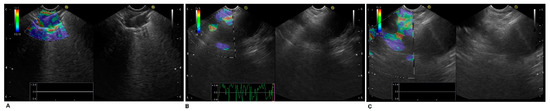

2.3. Endoscopic Ultrasound Technique